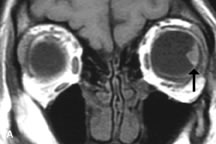

Cystic Lesions

Dermoid cysts appear as rounded, well-defined lesions typically contiguous with an orbital bony suture. The high-intensity signal on T1-weighted images is attributed to the sebaceous-produced lipid contents (Fig. 18).31,50 Mucoceles may demonstrate a hypointense or hyperintense signal on MR images, depending on the concentration of proteinaceous or inflammatory fluid components. The integrity of the bony walls of the expanded sinus cavities cannot be assessed on MR as well as by CT.37,50,55,56 A high-signal intensity on Tl- and T2-weighted images is characteristic of orbital chronic hematic cysts because of the blood-breakdown products within the cysts.57

Fig. 18. A. T1-weighted, (B) T2-weighted fat-suppressed, and (C) T1-weighted fat-suppressed MR scans demonstrate a small dermoid cyst arising near the palpebral portion of the lacrinal gland (arrows). The lesion is similar in signal intensity to fat on the T1-weighted scan (A) consistent with a high adipose tissue content. The lesion shows fat-suppression and low signal intensity on the two fat-suppressed sequences (B and C) confirming its high lipid content.